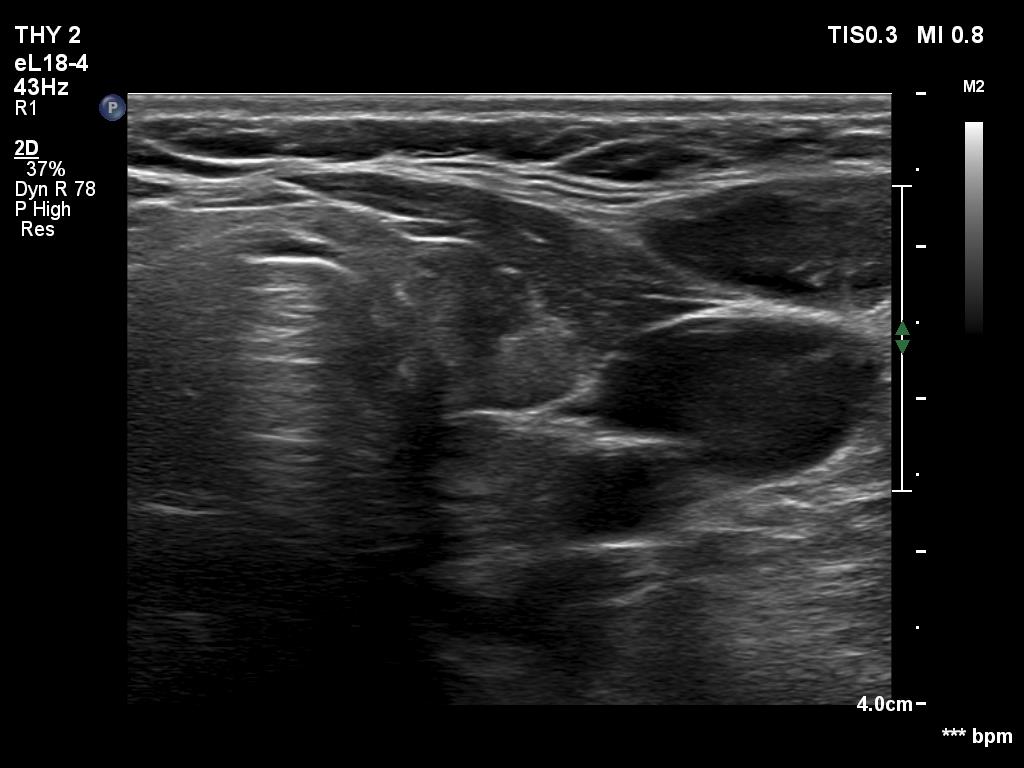

Second examination 2 years later (third rows of images):

Palpation: Both lobes were a bit firm on palpation. There was a not firm nodule in the right lobe.

Both the ultrasound and the cytological patterns remained unchanged.